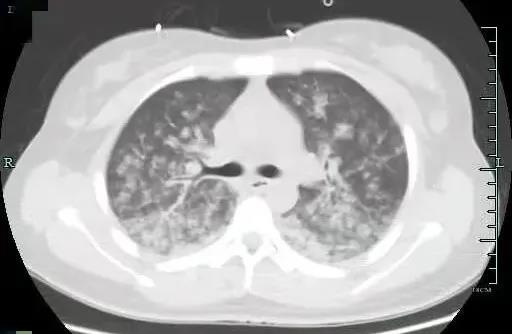

肺里一片“暴风雪”

两种原因造成的结果相似,但治疗方案截然不同。根据小月的肺动脉CTA、肺部CT等检查结果显示,小月为肺脂肪栓塞,此时小月的肺部已是白茫茫一片,就像暴风雪一样,脂肪进入她肺部,刺激血管发生痉挛,产生严重的炎症因子风暴!